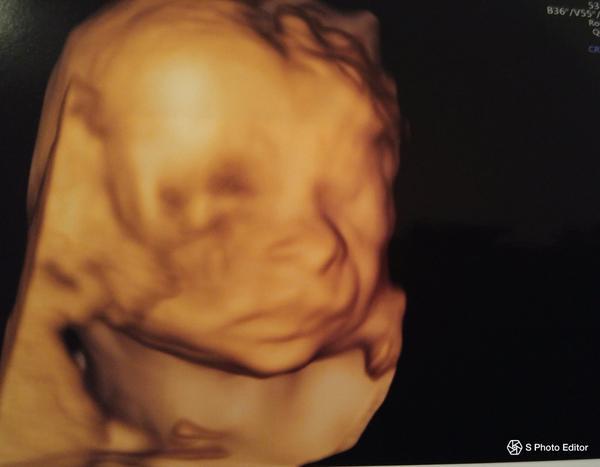

@heregova jeej,viem sI to predstavit,aj mne stale tisne slzicky ked vidim moju babu na sone...Blahozelam,hlavne vela zdravicka❤👶

@janinamojka dakujem,aj vam obom len to najlepsie❤️